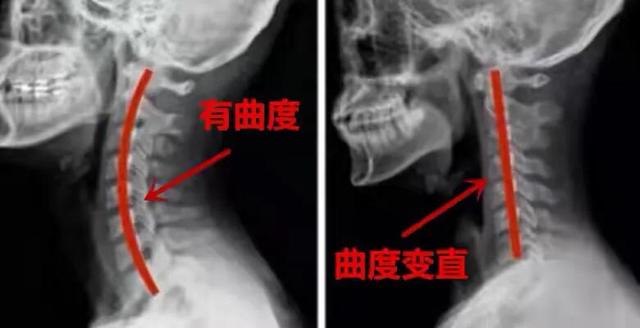

En fait, le cliquetis que vous entendez est le bruit des petites articulations de la colonne cervicale qui se remettent en place, ce qui indique également que votre colonne cervicale est dans un état extrêmement instable. Notre colonne cervicale est une section de la morsure ensemble, entourée par des ligaments, le renforcement de la capsule articulaire, de sorte que la situation générale est l'activité de la colonne cervicale n'est pas bruyante.

Cependant, après une longue période de tête basse ou avec l'âge, les petites articulations de la colonne cervicale autour des ligaments, la capsule articulaire se relâchent, il y a un désalignement des articulations, puis le mouvement du cou produit un bruit de cliquetis. De telles vertèbres cervicales sont sujettes à des chutes répétées sur l'oreiller, entraînant une hyperplasie et un durcissement des surfaces articulaires, voire une irritation ou une compression des racines nerveuses et des vaisseaux sanguins, de sorte qu'elles se transforment en spondylose cervicale.

Pour le clic cervical ou pour vous donner quelques suggestions : premièrement, il faut généralement étudier ou travailler pour réduire la tête basse, afin d'éviter une charge excessive sur la colonne cervicale ; deuxièmement, il faut dormir sur un oreiller de hauteur appropriée, la position du coussin doit être dans le cou, plutôt qu'à l'arrière de la tête, pour maintenir la courbure normale des vertèbres cervicales ; troisièmement, il faut renforcer les groupes de muscles centraux du cou pour améliorer la fonction de l'exercice, afin d'améliorer la stabilité des vertèbres cervicales.